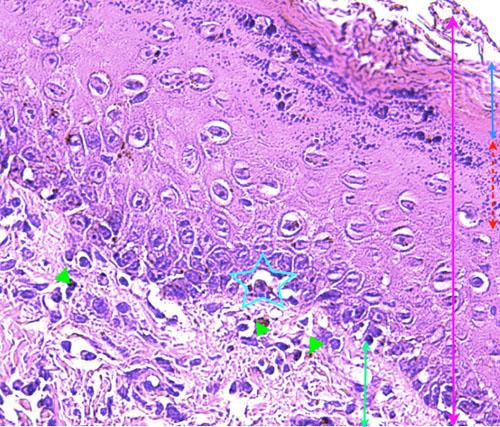

Photo 14 (Hémalun-Eosine X400): présence d’un infiltrat d’interface lymphocytaire

qui migre dans les couches les plus basales de l’épiderme. Le derme présente également un infiltrat périvasculaire.

Légendes de la Photo 14 :

- Double flèche bleue : couche cornée orthokératosique de l’épiderme

- Double flèche orange pointillée : épiderme (portion non kératinisée)

- Double flèche verte : derme

- Étoiles rouges : infiltrat lymphocytaire dans les couches les plus basales de l’épiderme (ici au sein de deux crêtes épidermiques)

- Triangles turquoises : infiltrat dermique mononucléé périvasculaire